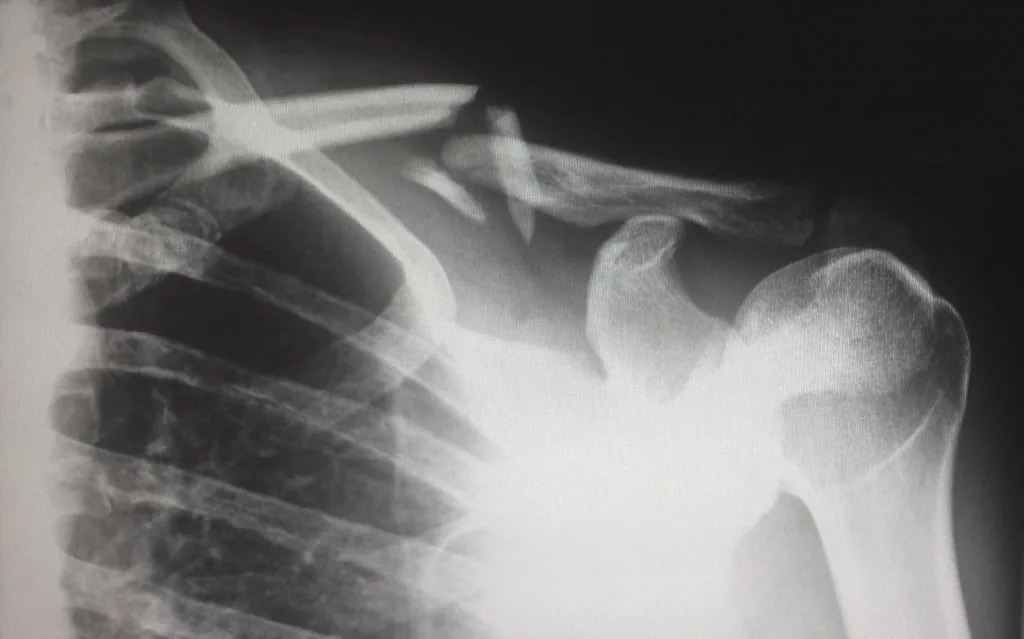

Humerus Fractures: Avascular Necrosis Can Be Serious

Complications of Humerus Fractures: Avascular Necrosis